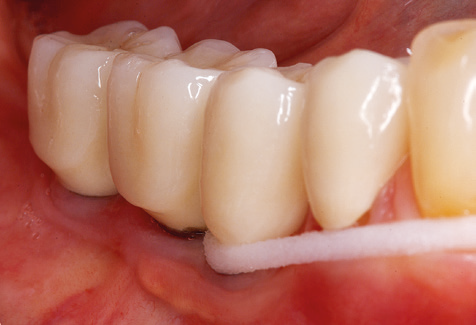

Eine 52­-jährige Patientin stellte sich nach Zahnverlust im 3. Quadranten erstmals 2004 vor. Sie hatte den Wunsch nach einer prothetischen Neuversorgung. Im Rahmen der parodontologischen und radiologischen Diagnostik zeigte sich ein ausgeprägter parodontologischer Behandlungsbedarf. Die Zähne 48, 28, 27 zeigten zudem eine infauste Prognose und wurden entfernt (Abb. 1). Nach der erfolgreich abgeschlossenen systematischen PAR­Therapie wurde eine festsitzende implantatprothetische Versorgung mit Insertion von fünf Implantaten in Regio 35, 36, 37 und 46, 47 durchgeführt. Die prothetische Versorgung der natürlichen Zähne erfolgte mit verblendeten Zirkonoxidkeramikkronen, die Implantate wurden mit zweiteiligen individuellen Zirkonoxidabutments und ebenfalls verblendeten Kronen aus einer Zirkonoxidkeramik versorgt (Cercon base colored, Dentsply Sirona Lab). Die definitive Insertion der prothetischen Versorgung erfolgte im Jahr 2005.

Im Rahmen der Zehn­Jahres­Kontrolle zeigten sich keine Hinweise auf einen fortschreitenden parodontalen Attachmentverlust oder einen periimplantären Knochenverlust (Abb. 3).

Abb. 3: Panoramaschichtaufnahme nach einer prothetischen Funktionsperiode von zehn Jahren.